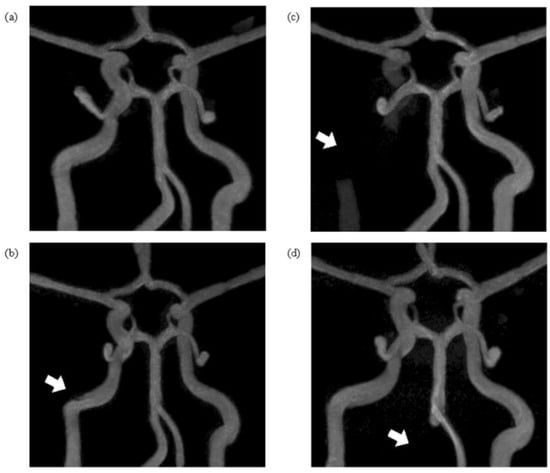

The 3D TOF MRA images clearly showed the morphological information for each modeled vascular disease (Figure 4). For the normal model, flow was observed in all vessels except for the Acom. Flow was similarly observed in the ICA50 stenosis model, but that model showed a narrowed vessel segment in the area where stenosis was present. For the ICA100 occlusion model, no blood flow was observed in the area where the vessel was blocked, but normal flow was observed in the other vessels. Furthermore, the flow in the Acom, which was difficult to detect in the normal model, was identified in this model. For the VA100 occlusion model, no flow was observed in the right VA, where the occlusion was located. Blood flow was observed in both Pcoms for all models, but in the Acoms, blood flow was observed only in the ICA100 occlusion phantom.

Figure 4. Time-of-flight (TOF) MRA maximum intensity projection (MIP) images of each vascular model: (a) normal phantom; (b) right ICA 50% stenosis phantom (ICA50); (c) right ICA 100% occlusion phantom (ICA100); and (d) right vertebral artery (VA) 100% occlusion phantom (VA100). The reconstructed TOF MRA images from each phantom were visualized using maximum intensity projection (MIP) in the coronal plane. The white arrows indicate the regions where cerebrovascular disease was modeled.